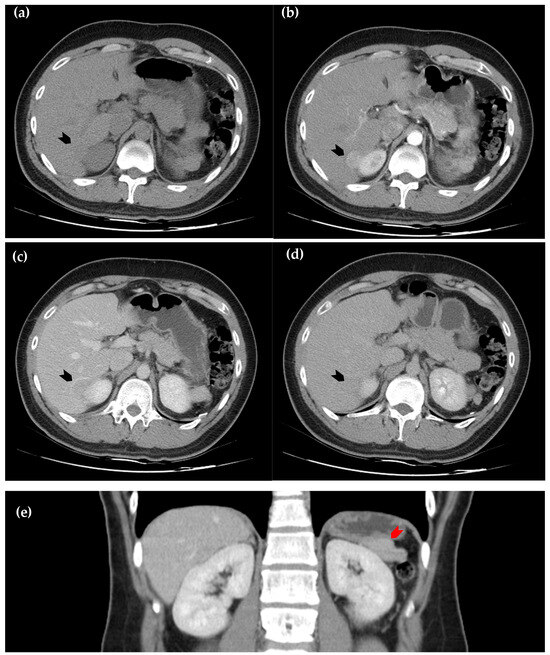

Figure 1. Dynamic computed tomography of the liver. (a) Axial view of the pre-contrast sequence shows a slightly hypodense lesion, as compared with the surrounding normal hepatic parenchyma, located in segment six of the liver (black arrowhead); (b) axial view of the arterial phase. The lesion exhibits homogeneous enhancement (black arrowhead); (c) axial view of the portal phase, in which the lesion becomes relatively hypoattenuating (black arrowhead); (d) the axial view of the delayed phase, in which hypoattenuation of the lesion persists but is less prominent than in the portal phase (black arrowhead); (e) coronal view of the portal phase, in which a soft tissue lesion at left perinephric area (red arrowhead) demonstrates similar attenuation to the intrahepatic lesion, raising suspicion for splenosis. However, due to the early wash-in and early wash-out enhancement pattern, hepatic tumors such as hepatocellular carcinoma and metastatic lesions remain important differential diagnoses [1,2,3,4].